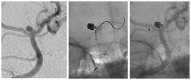

Introduction: The Neuroform Atlas Stent System is a recently introduced modification of the original Neuroform Stent System consisting of a hybrid design with open and closed cells. Initial experience, technical considerations and treatment outcomes including 1-year follow-up using the Atlas stent in combination with coil embolization are reported.

Material and methods: Thirty patients with 30 unruptured aneurysms were treated with stent reconstruction. Immediate, 4-month and 12-month post-treatment angiography and clinical assessment were performed.

Discussion: In 29 cases, the stents were delivered and positioned without difficulty in deployment. Technical complications occurred in one patient related to advancement of the stent during delivery. One procedure-related clinical complication occurred with no permanent neurological deficit. On immediate post-treatment angiography, 29 of 30 aneurysms showed Raymond Class I or Class II occlusion. At 1-year follow-up, all 30 patients were clinically stable and 18 of 30 aneurysms showed Raymond Class I complete occlusion. Retreatment was performed in two patients with residual aneurysm.